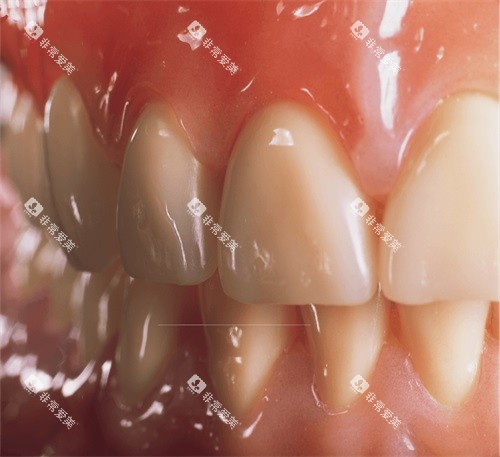

全瓷牙冠在金华地区的收费是 2000 - 4500 元/颗。

全瓷牙冠之所以受到很多人的喜爱,是因为它具有美观、生物相容性好等特点。

全瓷牙冠的颜色和透明度与天然牙齿非常接近,几乎可以达到以假乱真的结果,不会影响患者的美观。

而且,它不含有金属成分,不会对牙龈组织产生刺激,减少了牙龈发黑等问题的出现。

在口腔内的稳定性也比较好,能够非常好地修养牙齿的咀嚼功能。

全瓷牙冠的价格差异主要与材料有关。

一些高端的全瓷材料,如二氧化锆全瓷,其强度和美观度都更高,价格也就相对较贵,可能接近 4500 元/颗。

而一些普通的全瓷材料,价格则会相对较低,大概在 2000 元/颗左右。